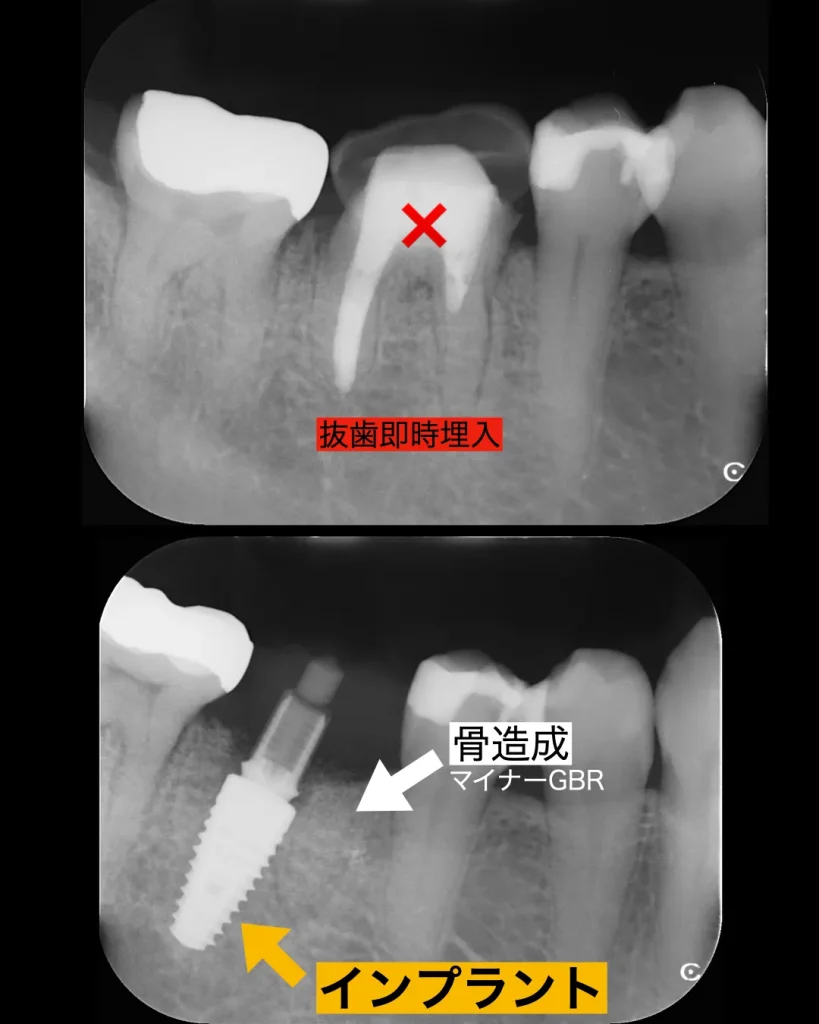

当日は、まず、破折した歯を周りの歯肉を傷つけず繊細に抜歯を行いました。方法は中央で2つに分割して前根と後根に分け一つずつ抜歯することによって周りの骨の削除を減らし歯肉を傷つけることはしません。その後はインプラント窩をインプラント用ドリルにて形成しました。前方は歯牙の破折により、骨が溶けており膿があったのでしっかりと掻爬を行い、インプラントは後方の根の方に近くに埋入しました。抜歯したその日にインプラントを入れる事を抜歯即時インプラントと言います。今回のその抜歯即時インプラントで手術を行いました。

前の根は骨が溶けていたので、抜歯した後はマイナーGBRを行いました。

マイナーGBRとは、インプラントを埋入すると同時に行う小規模な骨造成のことを指します。本来GBRは一度歯茎を閉じて6〜8ヶ月ほど待ってからインプラント埋入することが多いですが、マイナーGBRはインプラント埋入と同時に骨を入れるので待ち時間がありません。その分、処置が難しくなり経験と技術が必要となります。

当院では痛みを極力少なく、治癒期間の短縮による患者様の負の状態を極限まで減らすことを目的としております。その中でも抜歯即時インプラントは歯を抜くこと、そしてインプラントを入れることを同日に行うことにより手術を一回で済ませることができます。ただし、抜歯窩の治癒を予測し、さらに骨の形態が不完全なままインプラント埋入ができる技術が必要です。

今回のインプラント手術は簡単そうに見えて、実は抜歯即時インプラント埋入とマイナーGBRを同時に行っており、熟練した技術が必要な手技となります。